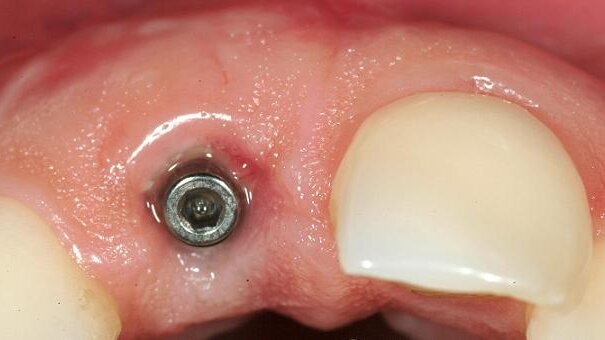

Owing to pulsating pain and the previous endodontic treatment, the tooth was considered hopeless with regard to an optimal long-term outcome and was to be extracted. The X-ray examination confirmed a chronic infection around the apex. The soft tissue was intact with a satisfactory attachment level to the neighbouring teeth. The quality of the rather thick gingiva was good. The incision for the apex resection had resulted in scar tissue at the junction of the keratinised and non-keratinised gingiva. Tooth #21 had been filled with a four-side composite filling at the mesial side.

Since the expectations of the patient regarding the aesthetic outcome were very high, we decided on immediate implant placement with a CAMLOG SCREW-LINE Implant after extraction of tooth #11. The soft- and hard-tissue structures were preserved as far as possible. Bone augmentation was performed at the time of implantation to treat the bone defect. The prosthetic treatment was to take place three to six months post-operatively, depending on the size of defect.

We aimed to preserve the soft- and hard-tissue structures to achieve an adequate level of marginal gingiva together with an adequate interdental bone peak. Therefore, we decided on immediate implant placement after extraction of tooth #11, creating optimal soft- and hard-tissue structures around the implant at the time of implant placement. The soft tissue around coronal part remained untouched and the coronal aperture was closed with a transmucosal abutment. The flap preparation was performed in the apical region only. This technique was chosen to provide the best possible interface between crown and gingiva.